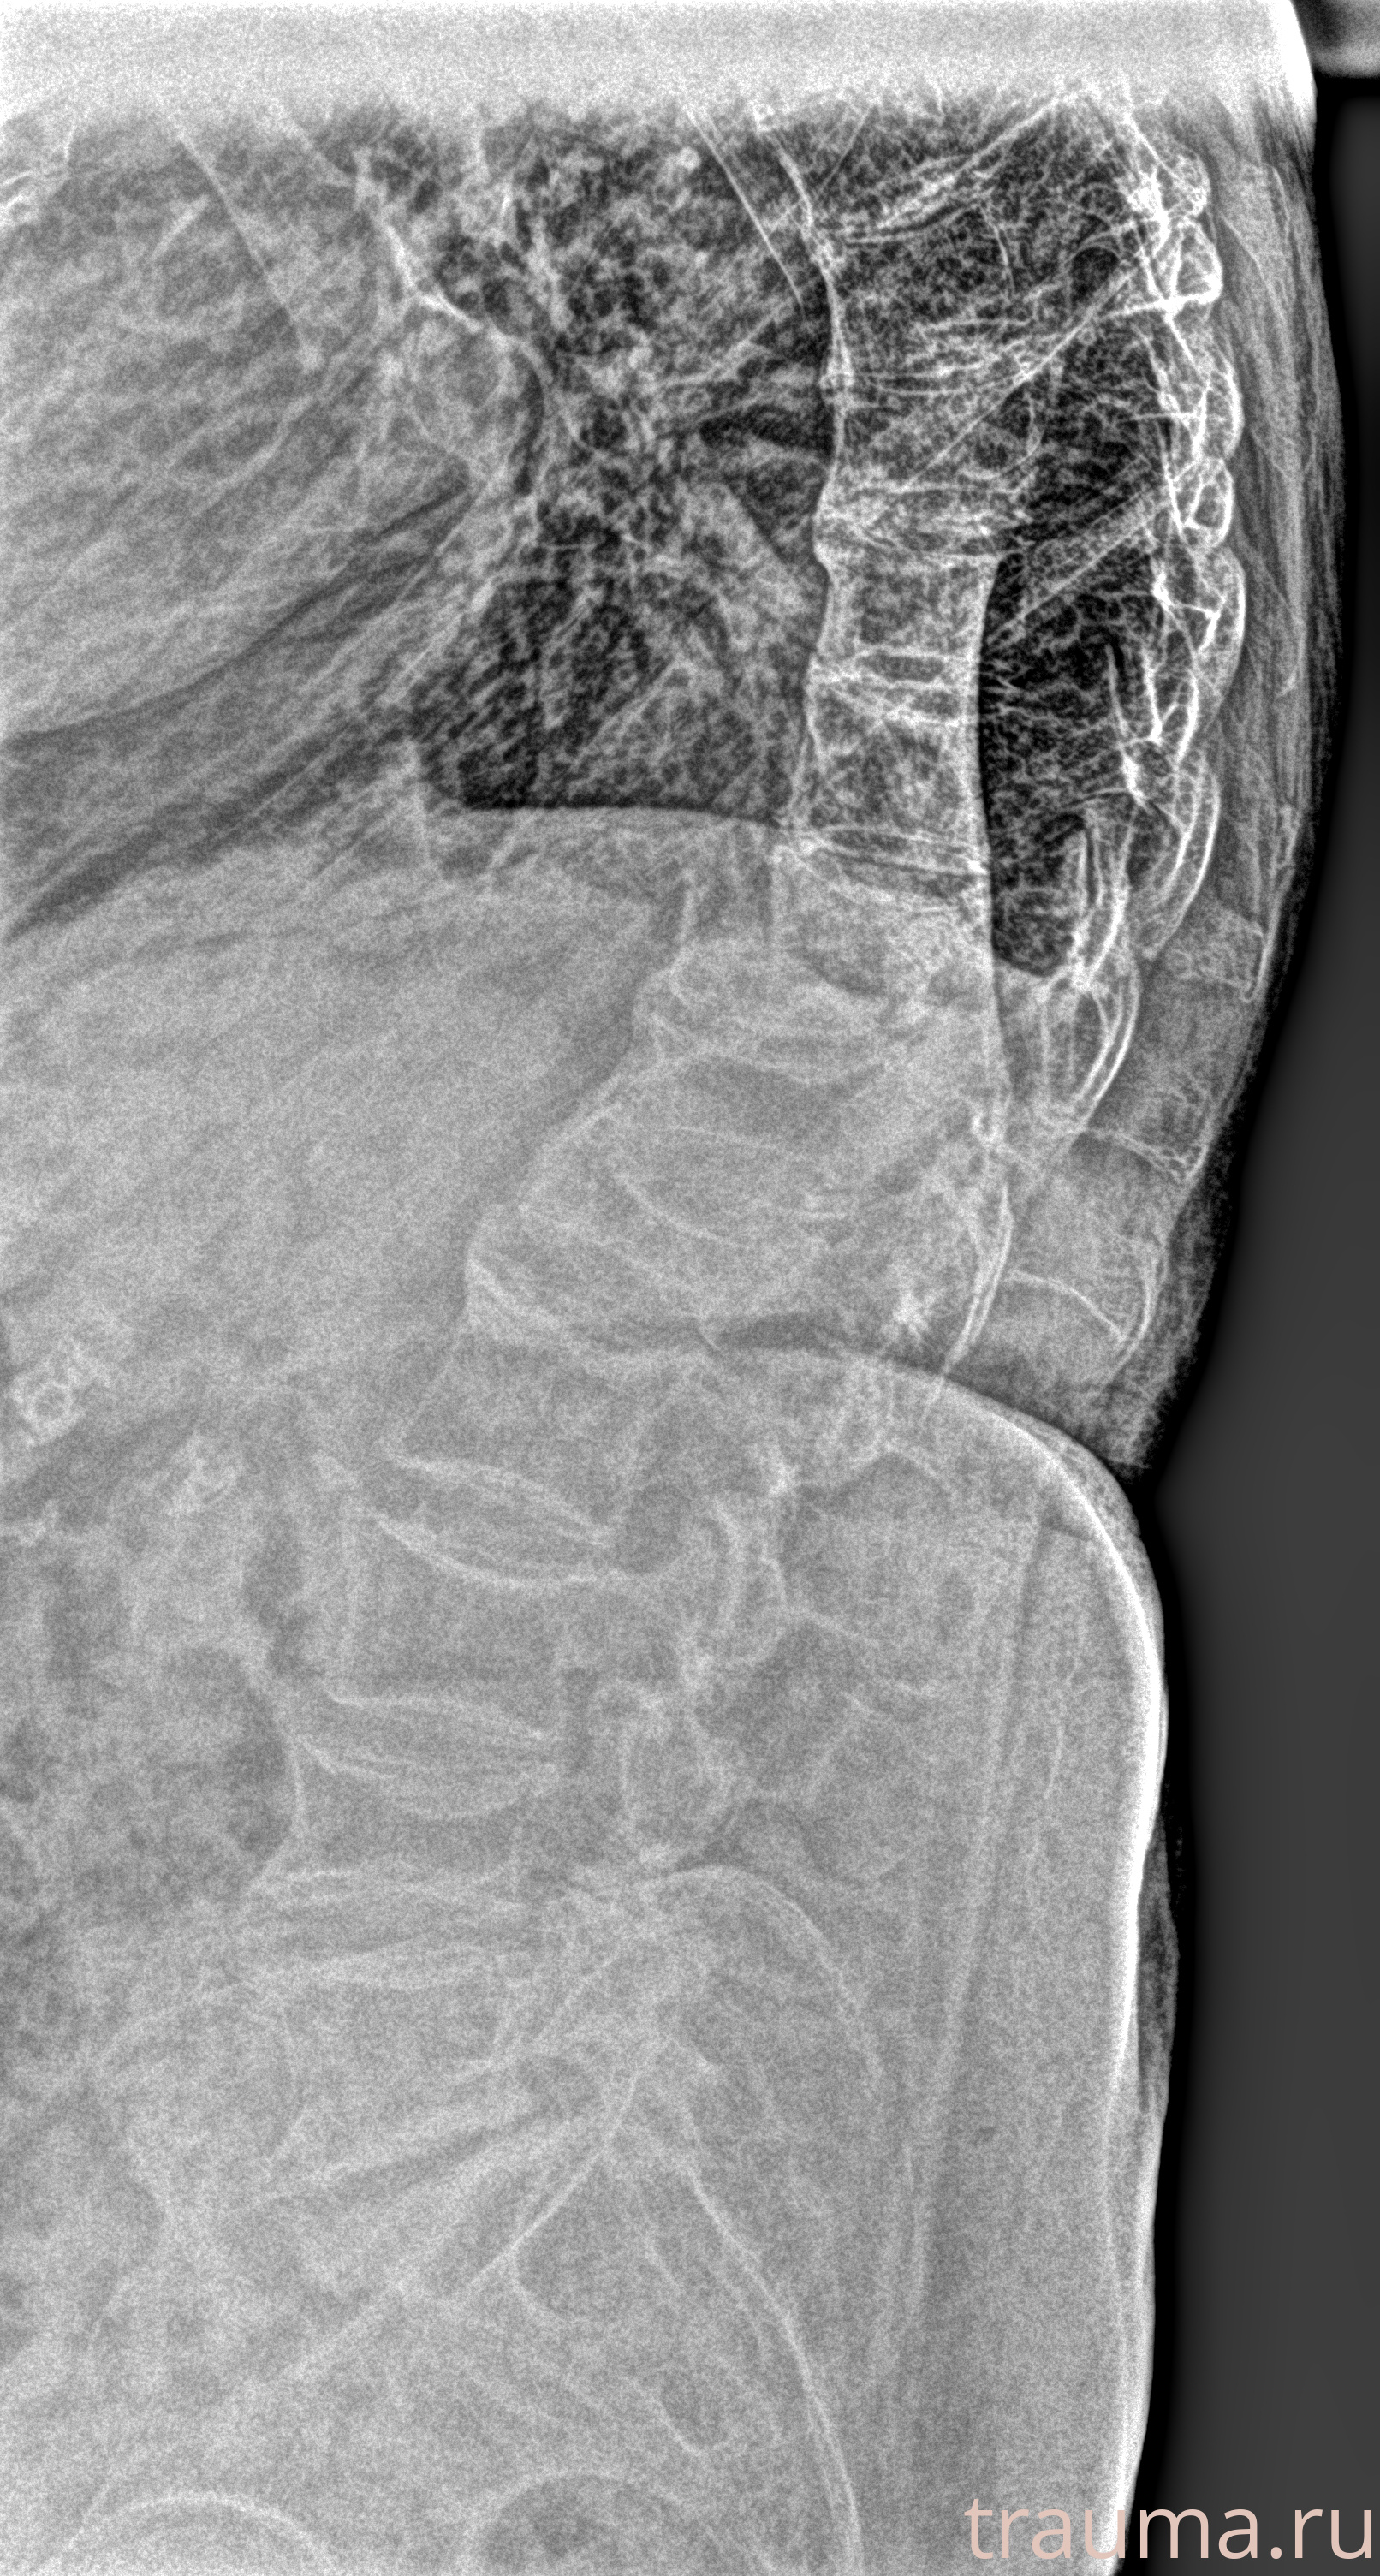

Рентген на дому: по вашему адресу приезжает врач-рентгенолог, травматолог-ортопед с мобильным рентгеновским аппаратом, проводит диагностику травмы или заболевания, делает необходимые рентгенограммы, дает рекомендации по дальнейшему лечению. Получить качественные снимки в домашних условиях возможно благодаря уникальной методике, разработанной МосРентген Центром для института  Склифосовского